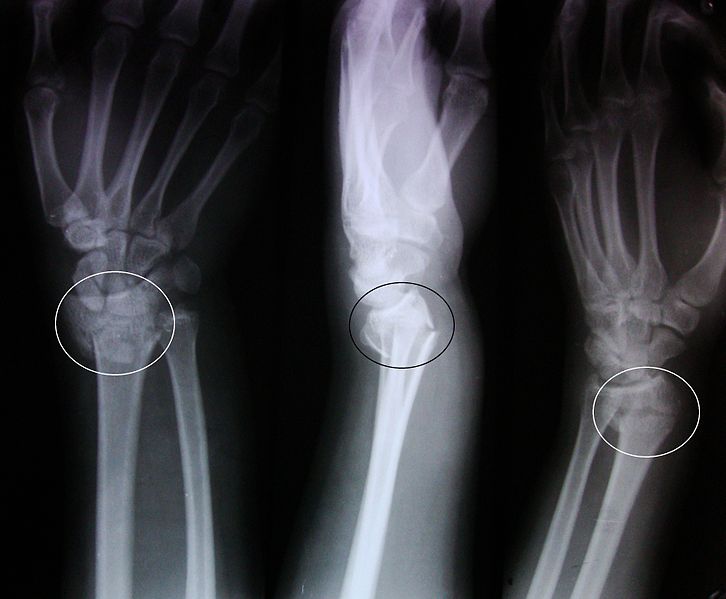

Dinner Fork Deformity Fracture . — a dinner fork deformity, also known as a bayonet deformity, occurs as the result of a malunited distal radial fracture,. It’s also known as a distal radius fracture,. Young patients (sports/trauma) and elderly patients (osteoporosis/low energy trauma). a colles’ wrist fracture occurs when the radius bone in your forearm breaks. Common upper limb injuries, often due to falls onto an outstretched hand (foosh). — key points. — in the distal radius, the term 'colles’ fracture' is still used to describe a fracture in which there is an obvious and. The smith’s fracture is essentially the opposite of the colles’.